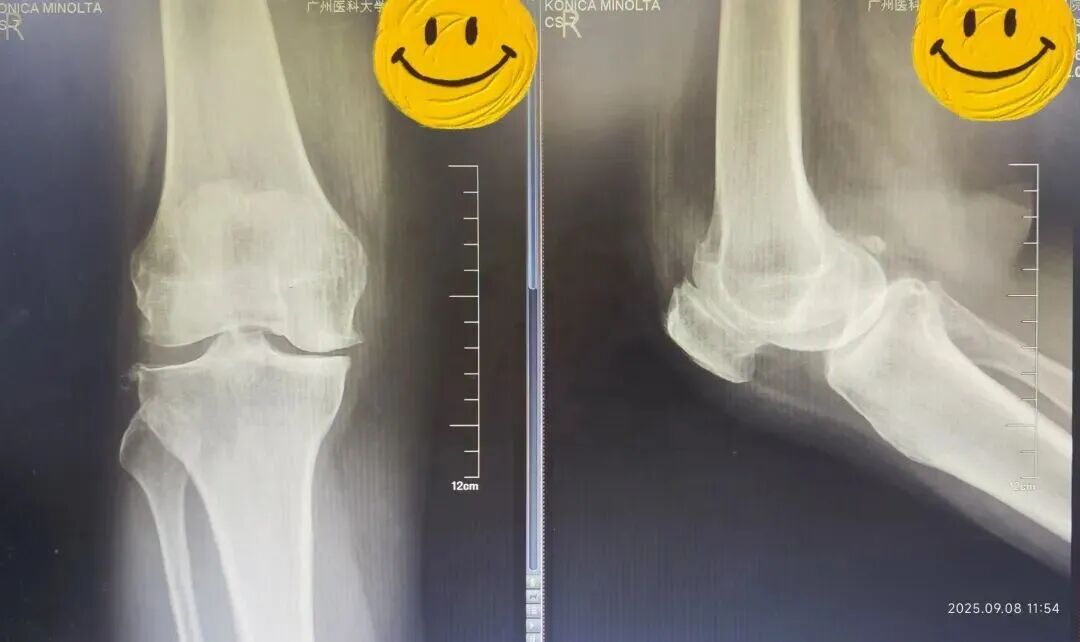

接诊的骨科主任陈东峰发现,温女士左膝关节轻度肿胀,关节活动受限,有疼痛症状,结合影像学表现,符合膝关节退行性骨关节病的典型特征,建议她入院治疗。

在麻醉科配合下,陈东峰手术团队清除了增生的滑膜组织,去除了骨赘,对关节进行了适当松解,术中发现关节面磨损严重,软骨下骨暴露,内侧半月板后角脱位。医生精心安置了人工关节假体,替代了已经损坏的关节面。

术前(左)术后(右)X线光片对比